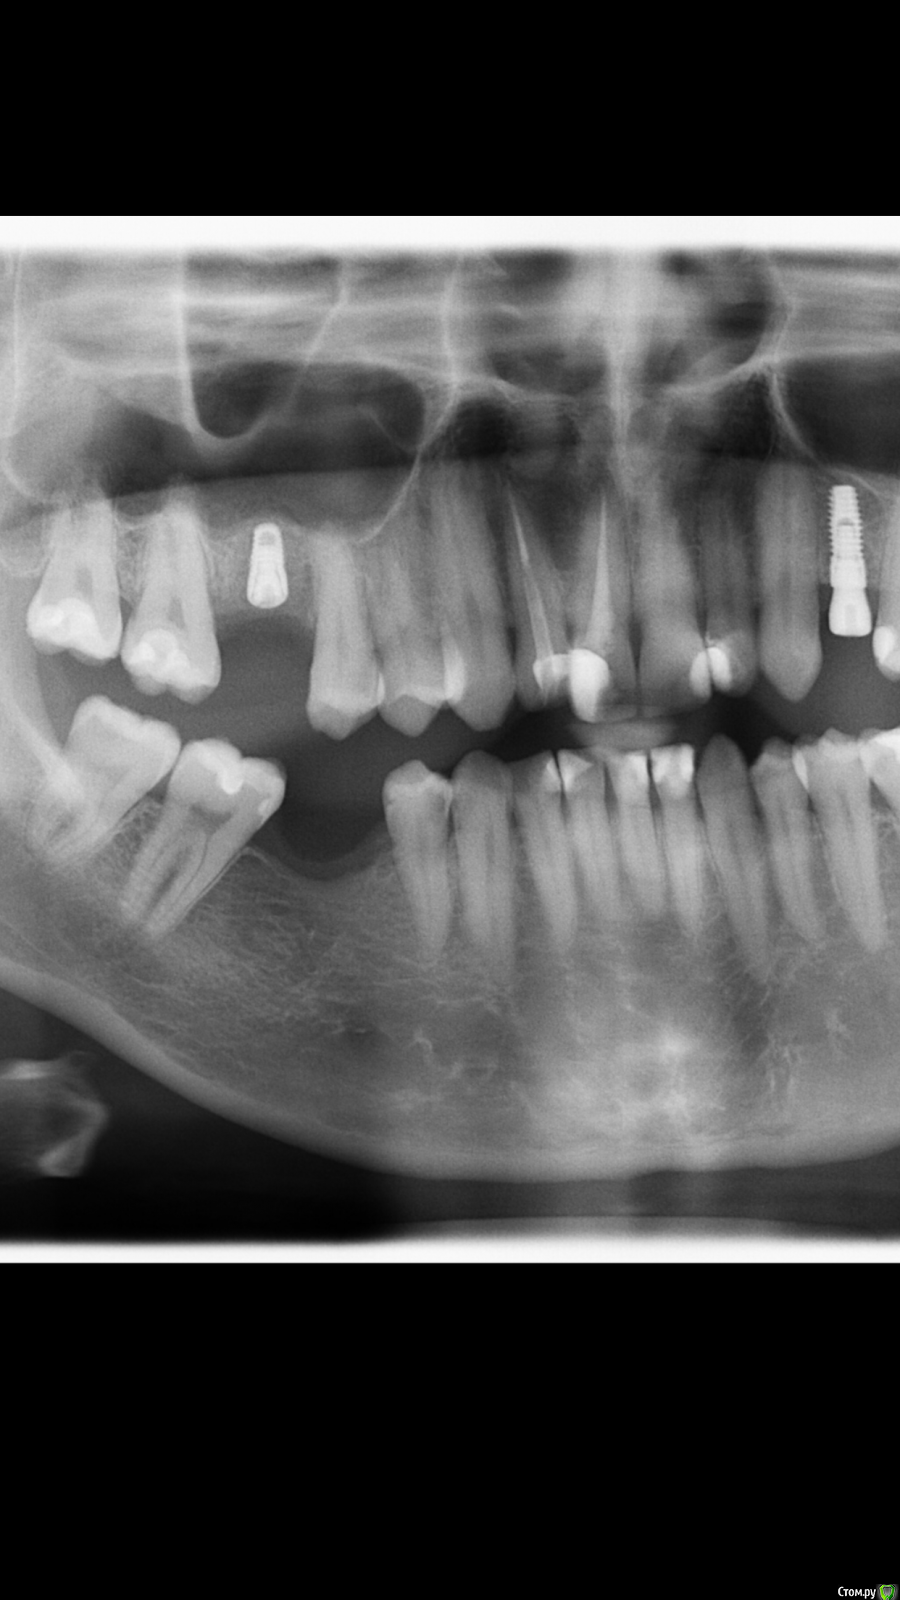

DrDimedrol Опубликовано 5 июня, 2020 Поделиться Опубликовано 5 июня, 2020 (изменено) На самом первом кейсе похоже на перегрев, вокруг апекса импланта на первых снимках есть характерная картинка (2-3-4-ий снимок). Ирригация слабая или агрессивная сверление. Изменено 5 июня, 2020 пользователем DrDimedrol Ссылка на комментарий

ilnurik Опубликовано 5 июня, 2020 Автор Поделиться Опубликовано 5 июня, 2020 На самом первом кейсе похоже на перегрев, вокруг апекса импланта на первых снимках есть характерная картинка (2-3-4-ий снимок). Ирригация слабая или агрессивная сверление.Одномоментная имплантация на первом кейсе. может в спортивный зал начали ходить?Если бы, не могу себя заставить Ссылка на комментарий